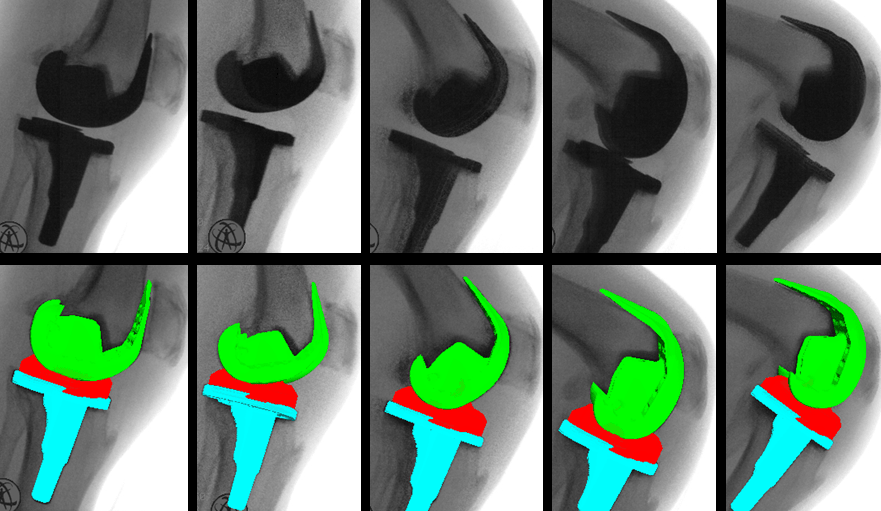

Fluoroscopy Evaluation

Researchers employed video fluoroscopy to examine the femorotibial contact patterns in subjects who underwent either posterior cruciate retention or posterior cruciate substitution total knee arthroplasty. They analyzed the femorotibial contact of many individuals with different types of total knee replacements performed by various surgeons. Using successive deep knee bends at different angles, video images were captured and processed.